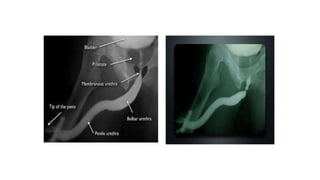

Retrograde Urethrography

Position

โ€ข Exposures are made with the patient

in a 45-degree oblique position lying

on either side and the dependent

thigh acutely flexed with penis

placed in slight tension.

Interpretation

โ€ข If the radiopaque contrast is injected properly, the entire anterior and

posterior urethra should be filled with contrast and seen to jet into the

bladder neck.

โ€ข The verumontanum is seen as an ovoid filling defect in the posterior

urethra

โ€ข The distal end of the verumontanum marks the proximal boundary of

the membranous urethra and constitutes the urethra that passes through

the urogenital diaphragm.